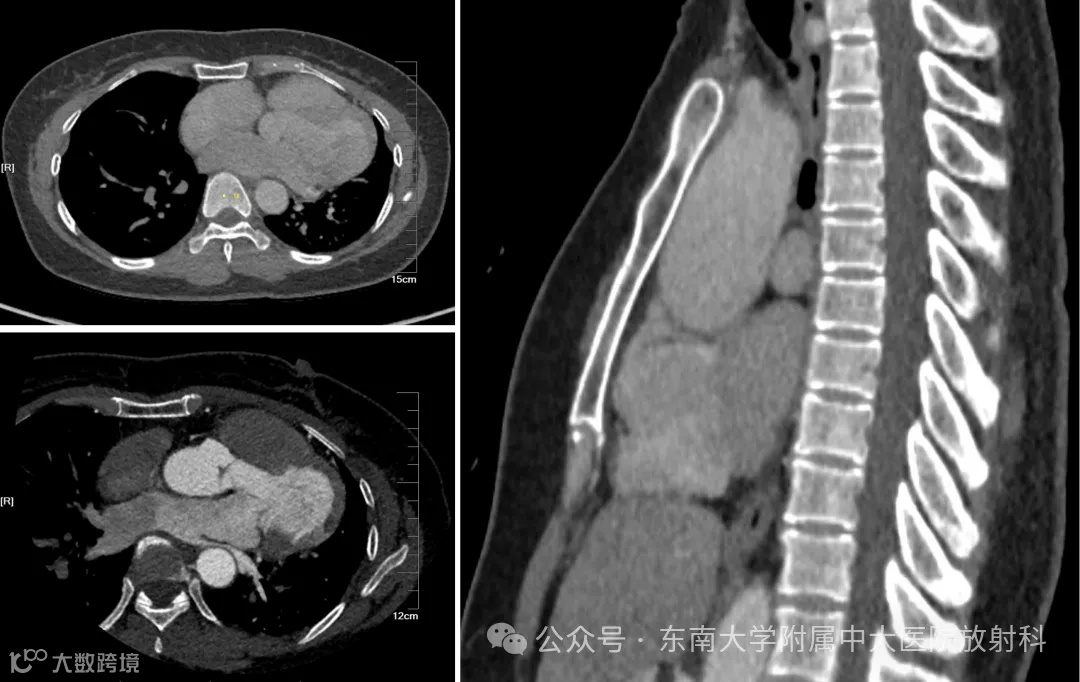

病例2

性别:女 年龄:24岁

主诉:心慌半年,检查发现心脏瓣膜病1月余

现病史:患者半年前无明细诱因出现心慌不适,间断发作,无胸痛,无胸闷气喘,无咳嗽咳痰,无头晕头痛,无反酸嗳气,无腹痛腹胀,无双下肢水肿,无夜间不能平卧等不适,至当地医院就诊,检查心脏彩超提示二尖瓣粘液样变,中度关闭不全,三尖瓣中度关闭不全,主动脉窦增宽既往史:既往体健,无慢性病史

实验室检查:心肌损伤组套、心肌酶谱(组套)、血常规、生化全套、电解质、甲状腺功能(-)

专科检查:律齐,心尖部可闻及III/6级收缩期吹风样杂音

影像: 2023-12-18 胸部HRCT平扫

影像学表现